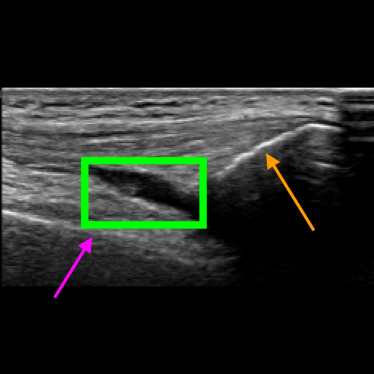

Figure 8 shows two US images that have been correctly classified by both approaches and that are relatively easy to classify by medical experts. Figure 8a shows an US image where the femur, the patella and the SQR are clearly visible, and the SQR is thin (i.e., not distended). On the other hand, Figure 8b shows an example of a Distended SQR. In this case, the SQR is clearly thick and hence distended.

Figure 8: Examples of images correctly classified by both solutions. The purple arrow points to the femur, the orange arrow points to the patella, and the green box indicates the SQR.

Figure 9 shows four examples of images that are more challenging to classify even by medical experts. This usually happens when there is noise in the US scan (as in Figure 9c) or when the SQR is borderline between Distended and Non-distended (as in Figure 9d). Figure 9a is correctly classified by both approaches as Non-distended. Figure 9b is correctly classified by the Multi-task approach but not by the Detection approach. Vice versa, Figure 9c is correctly classified by the Detection approach and not by the Multi-task approach. Finally, both solutions wrongly classify Figure 9d.